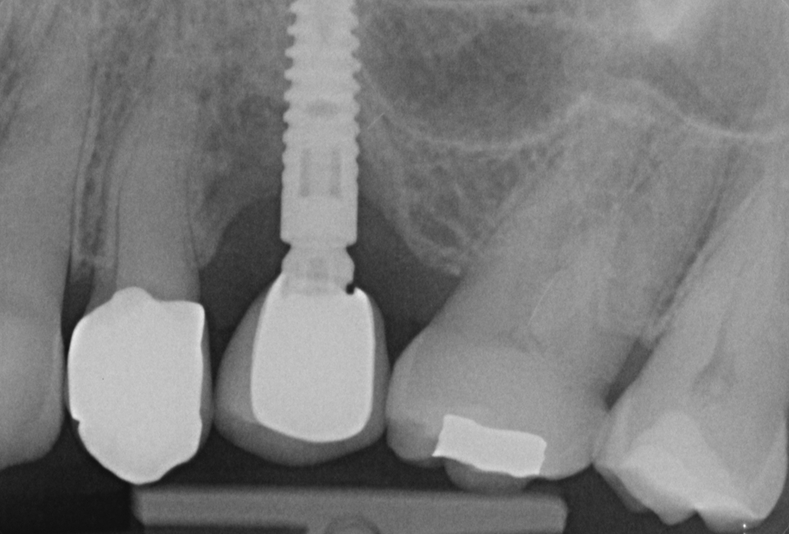

valutazione radiografica

Igiene dentale

Terapia non chirurgica di peri-implantite con fotodinamica di II generazione